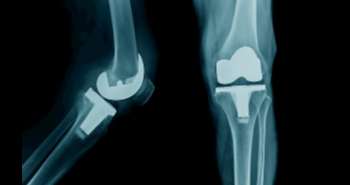

Correlation between smoking and fish intake with risk of rheumatoid arthritis

Attempts are proceeding to identify risk factors for rheumatoid arthritis (RA). Where smoking is an essential risk factor for RA, many individuals who never smoked also develop RA, this indicates the involvement of other factors such as diet and obesity as well. Other previous studies say that eating fish is a protective approach for rheumatoid arthritis (RA) risk possibly due to the anti-inflammatory influence of omega-3 fatty acid it contains, although this association has not been established explicitly. Therefore, this prospective cohort study was conducted with large sample size, repeated measures of dietary intake, and extended follow-up to assess the fish intake and RA risk by the age of onset, smoking and serologic status.